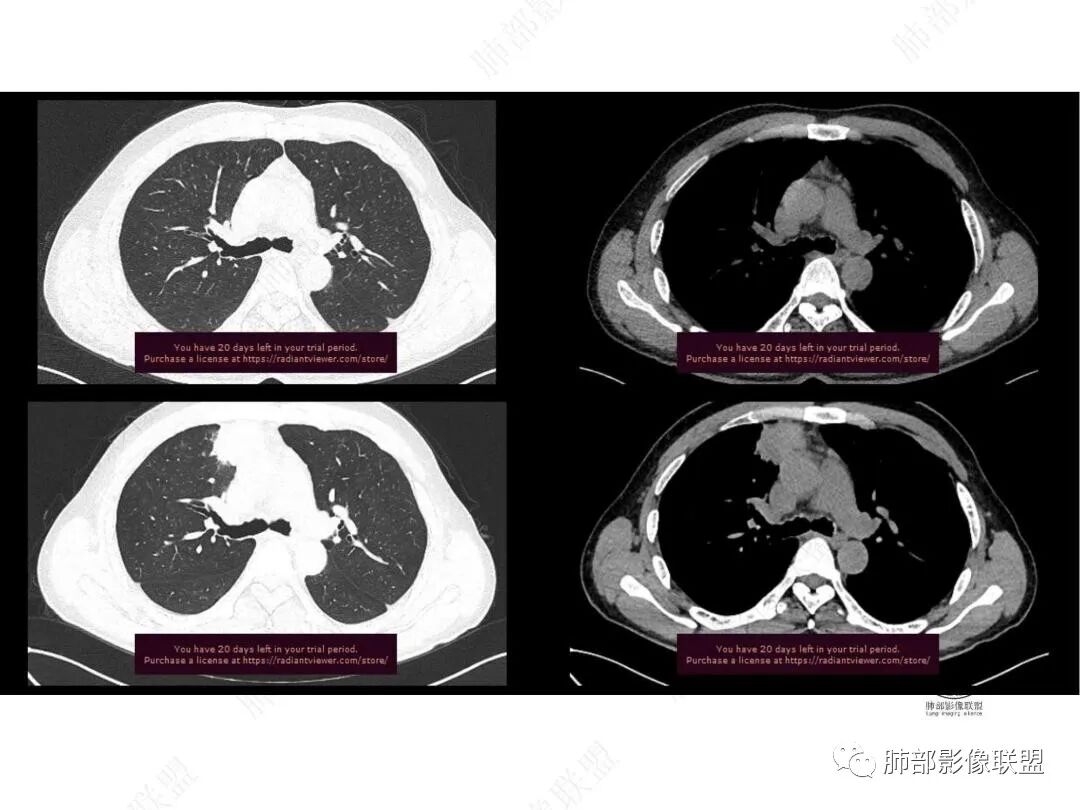

增强图像

肝脏病变明确,是轻度强化,延迟强化特点,边缘模糊,有轻微的包膜挛缩。

4.肝脏病灶没有假包膜,没有动脉早期强化,没有肝硬化,未见扩张胆管,未见环形强化,也未显示靶征,缺乏肝细胞肝癌、胆管细胞癌、转移癌或肝脓肿特征。

但回顾性分析,如此少血供确实可以符合淋巴瘤,如果密度更均匀一点的话,这是我们有所忽略的地方。